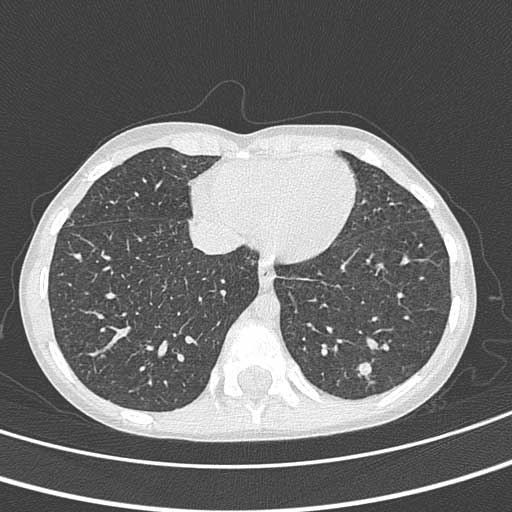

Fa un escreato e poi due aspirati gastrici perch� non ha tosse: tutti e tre negativi al diretto. Dal colturale di un aspirato gastrico � poi cresciuto il bK, per fortuna polisensibile. Avvia la terapia antitubercolare a quattro farmaci (rifampicina 300 mg/die, isoniazide 200 mg/die, pirazinamide 500 mg/die, retambutolo 400 mg/die) e a distanza di 4 giorni � asintomatico. La TAC torace mostra multiple opacit� nodulari millimetriche a distribuzione random compatibile con miliare tubercolare (mai avuta tosse). A 6 mesi dall�inizio della terapia RM encefalo: scomparsa dei tubercolomi; RM anca e TAC polmonare netto miglioramento delle lesioni. Angelo � stato in cura per un anno. Ora sta bene ma se si muove un po� pi� del solito l�anca destra gli fa male.

Tac Torace